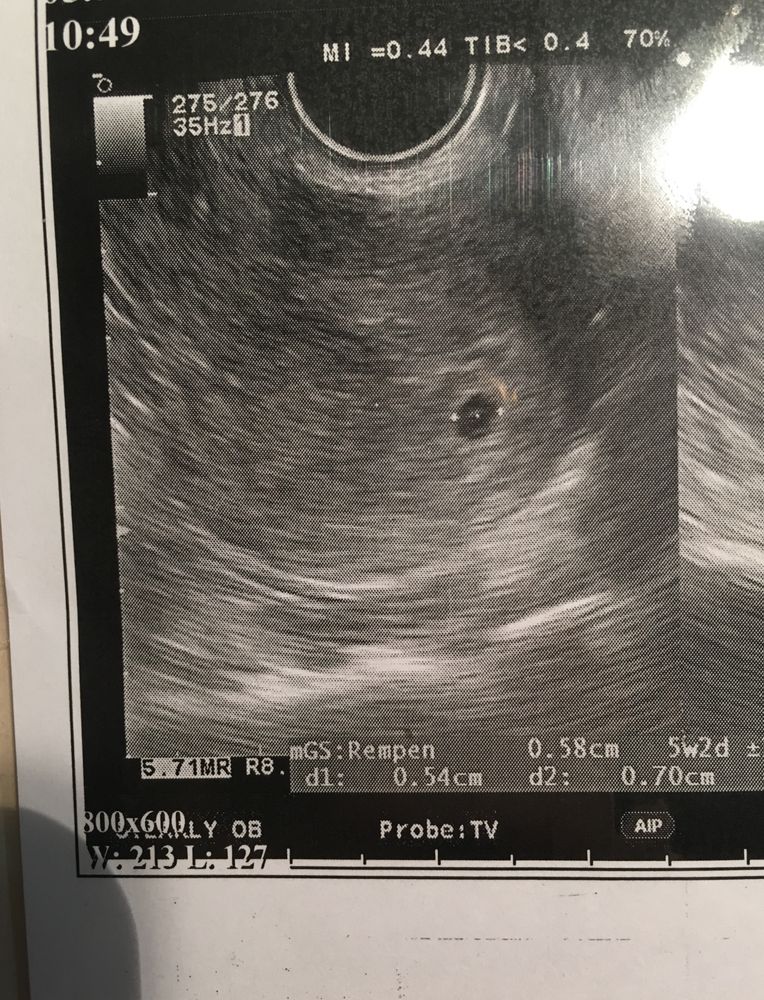

Девочки, помогите! Решила пересмотреть узи вчерашнее: смутила фраза, плодное яйцо в Лёвом углу полости матки 🤯 почитала в интернете, много пишут что это возле трубы самой, типа вб 😭🤯

вот узи

В матке нет углов) Есть дно и передняя/задняя стенка. Просто ПЯ не по середине, а ближе к левому боку. Всё хорошо) Вон уже ЖМ виден, значит эмбриончик вот вот вырастет до видимого на УЗИ размера)

Вы скорее всего прочитали про интерстициальную беременность, это когда плодное яйцо находится в месте впадения маточной трубы в матку, ткани там почти не растяжимы и прогноз у такой беременности обычно плохой. Это крайне редкая разновидность внематочной беременности и к вашей беременности не относится, если бы у вас это увидели на УЗИ, точно не стали бы настраивать на хорошее. У вас максимум плацента потом может быть по боковой стенке от этого и скорее всего она будет высоко.